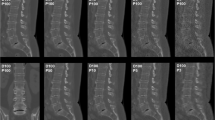

Virtual lowering of tube current and sparse sampling were successfully achieved in all patients (Figs. 1 and 2). A median of eight vertebrae (range 4–19 vertebrae) was captured by the FOV of MDCT scans, which covered the cervical spine in 20.0%, the cervico-thoracic spine in 8.6%, the thoracic spine in 5.7%, the thoraco-lumbar spine in 28.6%, and the lumbar spine in 37.1%. The average volumetric CT dose index recorded in the dose reports was 11.7 ± 5.7 mGy for original MDCT scans (Table 1), and was amounted 5.9 mGy, 2.9 mGy, and 1.2 mGy for MDCT with virtually lowered tube current or sparse sampling at 50%, 25%, and 10% of original data, respectively.

Virtual tube current reduction and sparse sampling in multi-detector CT (MDCT) of the cervical spine. Sagittal slices derived from full-dose MDCT (D100 P100), MDCT with virtually lowered tube current (D50 P100, D25 P100, and D10 P100), and MDCT with sparse sampling (D100 P50, D100 P25, and D100 P10) are shown in a patient with a cervical fracture (C2, dens fracture)

Overall image evaluation

Both virtual tube current reduction and sparse sampling led to decreased overall image quality, increased overall artifacts, and reduced contrast of vertebrae according to the evaluation of both readers (Table 3, Figs. 1 and 2, Supplementary Fig. 1). The assessed parameters were significantly different in MDCT with virtually lowered tube current and sparse-sampled datasets as compared to those in D100 P100 (p < 0.001; D100 P100 vs. D50 P100/D25 P100/D10 P100 and D100 P100 vs. D100 P50/D100 P25/D100 P10 of both readers).

When comparing MDCT with virtually lowered tube current to sparse-sampled datasets for overall image quality, sparse sampling resulted in significantly better scores according to each reader for all comparisons (p < 0.001, D50 P100 vs. D100 P50, D25 P100 vs. D100 P25, and D10 P100 vs. D100 P10 of both readers; Table 3 and Fig. 3). Similar findings with better scores for sparse-sampled imaging than for MDCT with virtually lowered tube current were observed for overall artifacts (p < 0.001, except for D50 P100 vs. D100 P50 for R2: p = 0.20; Table 3 and Fig. 3) and contrast of vertebrae (p < 0.001, except for D25 P100 vs. D100 P25 for R2: p = 0.005; Table 3 and Fig. 3). Good interreader agreement was observed for overall image quality, overall artifacts, and contrast of vertebrae, respectively (ICC > 0.80, R1 vs. R2 for D50 P100/D25 P100/D10 P100 and D100 P50/D100 P25/D100 P10; Table 3).